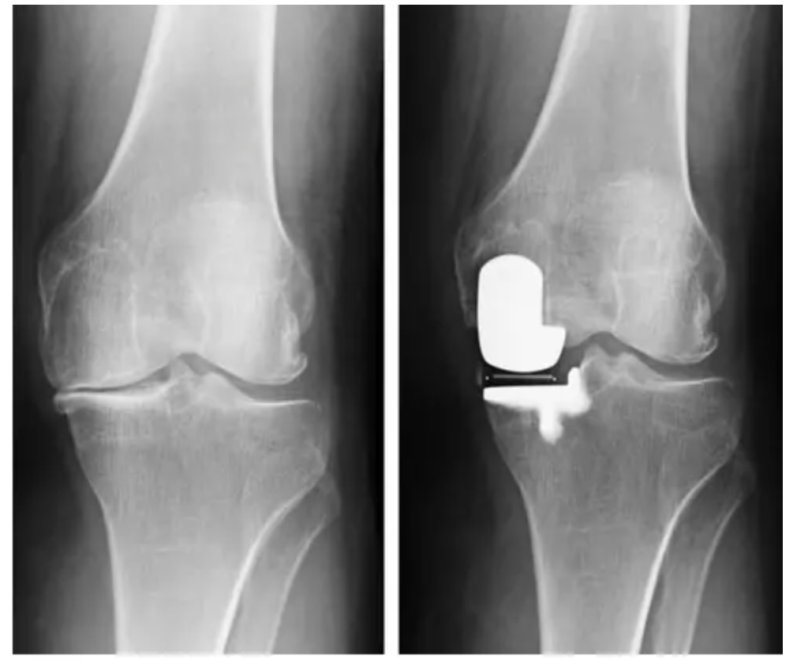

For Lindsey Vonn, surgeons planned an individual reconstruction tailored to the extreme demands of elite downhill skiing. Using high-resolution CT 3D scans, they were able to move beyond standardised, “one-size-fits-all” knee replacement, capturing the exact shape, density, and structure of her knee, including areas altered by years of injury and previous surgery.

Based on those scans, a digital twin model of Vonn’s knee was created, mapping the joint’s exact geometry, alignment, and rotational axes (the path along which force travels from the hip to the ankle). It allowed surgeons to analyse how her knee actually functioned rather than relying on population averages. The doctors had to assess varus (bow legs) and valgus (knocked knees) alignment, as well as the tibial slope (the angle of the top surface of the tibia relative to the horizontal), to determine how her knee was angled and tilted. They also had to identify subtle asymmetries that would be invisible on standard imaging but become critical under the high load. This level of precision was crucial, as even a one-degree misalignment can significantly overload cartilage and implants, especially under the extreme forces experienced in downhill skiing.

3D CT-based model individually designed to optimize implant placement in the sagittal, transverse and coronal planes. Photo credit to Strykier Mako Robotics

Partial knee implant replacing demaged tissues maximally preserving healthy structures. Photo credit to Journal of Isakos